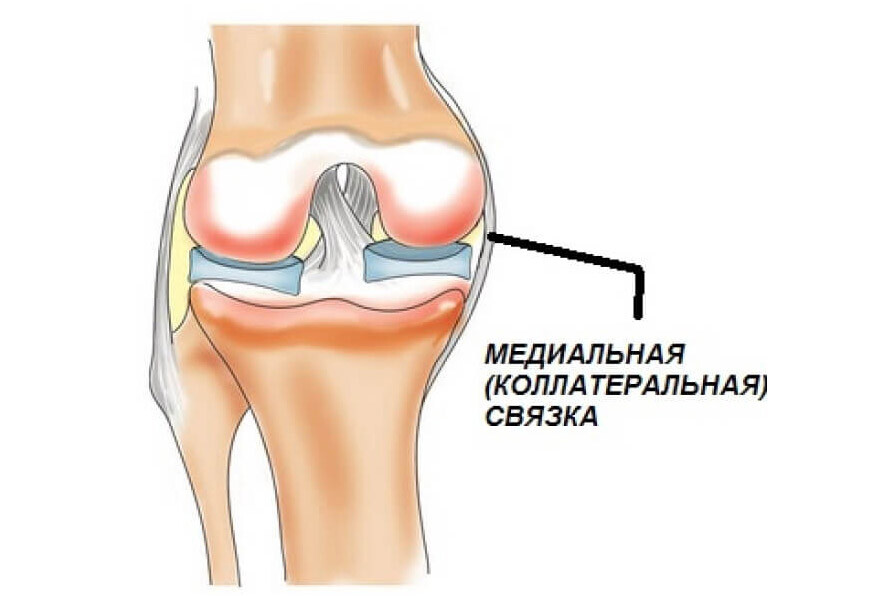

Анатомические изображения менисков и коленного сустава

Раздел: Иллюстрированные советы